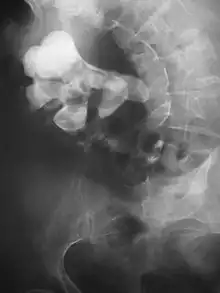

Calcium-containing stones are relatively radiodense (opaque to X-rays), and they can often be detected by a traditional radiography of the abdomen that includes the kidneys, ureters, and bladder (KUB film).[59] KUB radiography, although useful in monitoring size of stone or passage of stone in stone formers, might not be useful in the acute setting due to low sensitivity.[60] Some 60% of all renal stones are radiopaque.[61][62] In general, calcium phosphate stones have the greatest density, followed by calcium oxalate and magnesium ammonium phosphate stones. Cystine calculi are only faintly radiodense, while uric acid stones are usually entirely radiolucent.[63]

Bilateral kidney stones can be seen on this KUB radiograph. There are phleboliths in the pelvis, which can be misinterpreted as bladder stones.